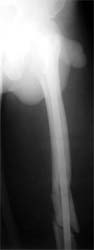

肱骨干骨折 采用闭合穿钉法,带锁髓内钉内固定,10个月后骨折愈合